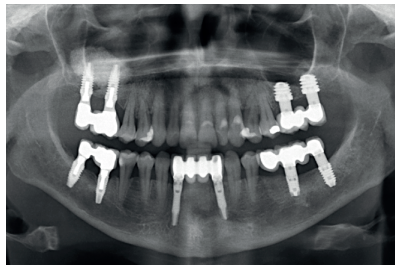

Finally, the stability of both treatments can be seen in the final X-ray at 8 years of age, where both are stable without bone loss (Figure 13).

In the clinical case described, both therapeutic alternatives show successful treatment for this clinical situation and this specific patient, and can be considered equally valid for resolving the vertical atrophy of the maxilla. For cases with a higher degree of vertical atrophy or those with different bone density and residual volume, the application of one or another technique must be assessed for the success of the treatment.